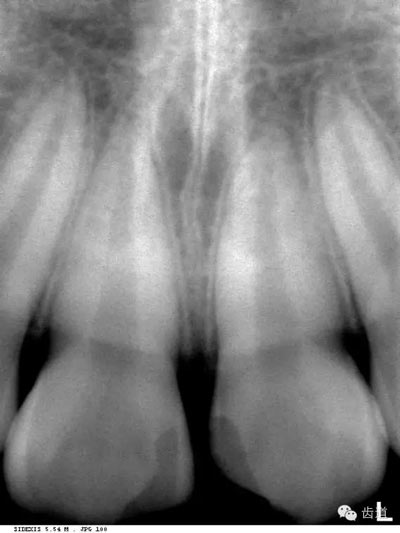

在兩個中切牙牙根之間或稍上方,多呈橢圓形密度低的影像,切牙孔影像可重疊在一側(cè)中切牙牙根尖處,易誤認(rèn)為根尖周病變,可視牙周膜和骨硬板是否完整加以鑒別

位于兩側(cè)中切牙牙根之間,由牙槽突向上,呈直線狀密度低的影像。其兩側(cè)為密度高的影像,為兩側(cè)上頜骨腭突的致密骨層。

鼻腔位于上切牙根尖的上方,顯示為對稱性半圓形密度低的影像,其中間被一密度高的骨隔分開為鼻中隔